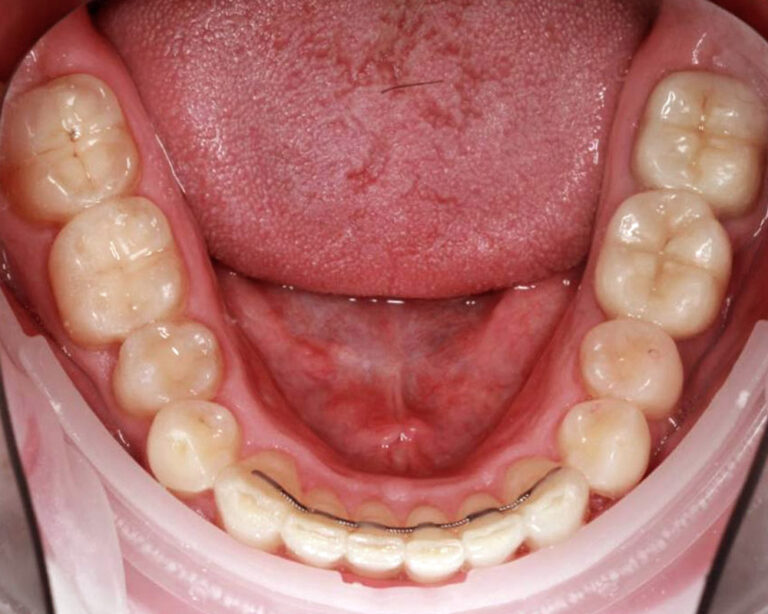

Кейс 12

Бирковская Екатерина Александровна

Количество кап ВЧ 24

Количество кап НЧ 41

ДО

ПОСЛЕ